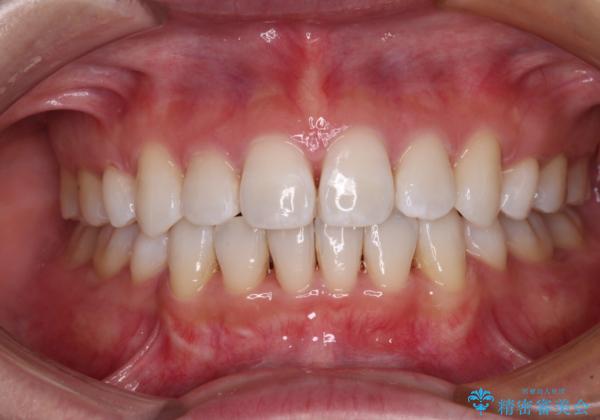

- 口元の突出感と口の閉じにくさを気にして来院された患者様です。

上下左右第一小臼歯4本を抜歯し、ワイヤー装置にて口元を引っ込めるよう矯正治療を行うこととしました。

2年~2年半が治療期間の目安でしたが、順調に治療が進み、1年9か月で満足のいく歯列となりました。